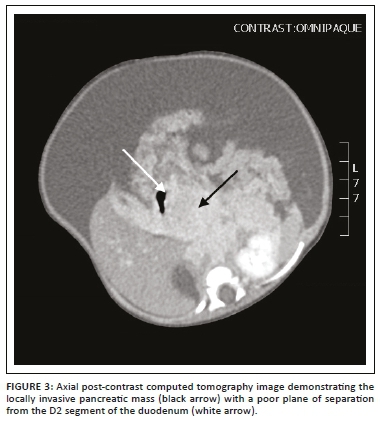

This was followed by a computed tomography (CT) scan of the abdomen and pelvis with an intravenous and oral contrast agent. Computed tomography imaging showed an ill-defined, enhancing mass in the head of the pancreas (Figures 1-3), with a poor plane of separation from the D2 segment of the duodenum (Figures 1 and 3). Enhancing soft tissue, which extended beyond the confines of the pancreatic head into the region of the porta hepatis, was also noted and appeared to be contiguous with this mass (Figure 1).

The differential diagnosis based on the imaging studies was that of a pancreatic vascular neoplasm; however, with the laboratory evidence of Kasabach-Merritt phenomenon (KMP), this prompted the diagnosis of a pancreatic KHE. Given the large size and peripancreatic extension of this lesion, a differential diagnosis of pancreaticoblastoma was considered; however, these lesions are typically heterogeneous in appearance with both cystic and solid components and often have calcifications.

On ultrasound, KHE appears as a homogeneous, ill-defined, soft tissue mass, which may be isoechoeic or hyperechoic compared to the pancreas, with associated mild to marked increased vascularity on colour Doppler.2,6 All previously reported cases described a mass in the head of the pancreas, as in this case report.6 Although the possibility of a vascular tumour could be suggested on US, a more specific diagnosis cannot be made because of the limitations in demonstrating the infiltrative portions and exact extent of KHE. Computed tomography and MRI together with magnetic resonance cholangiopancreatography (MRCP) are of added value in localising the mass, assessing the tumour extent and giving information of any associated findings such as dilation of the pancreatic and biliary ducts, duodenal obstruction and ascites. Leung et al. presented a case of a pancreatic KHE presenting with neonatal duodenal obstruction.1